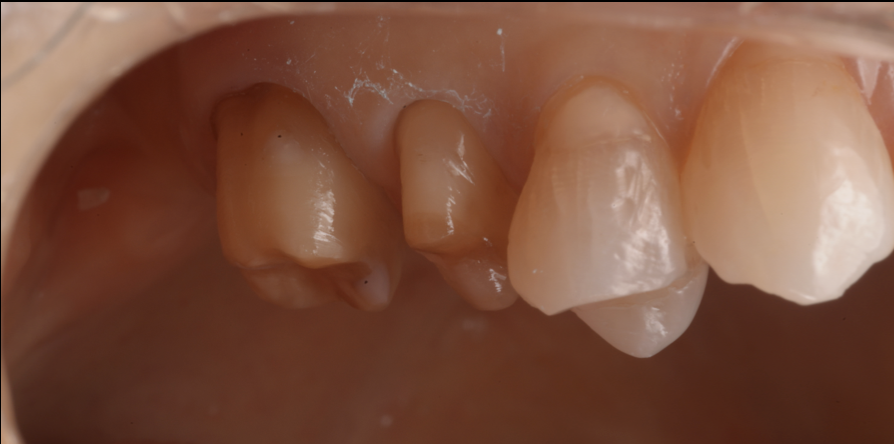

治療前後比較

治療前